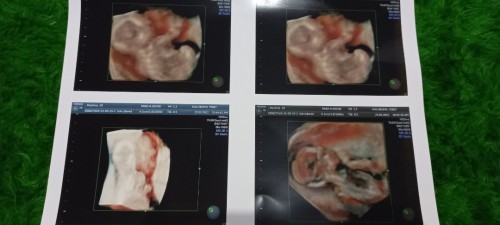

Ini kehamilan kedua anak pertama (kehamilan pertama janin q tdk berkembang 😢) Hri ini aq USG usia kandungan q 8weeks3day ,, bahagia sekali utk pertama x nya denger detak jantung janin ku, rasanya bener² seperti mujizat. 🥰🥰🥰 Semoga aq, janin ku serta bumil² yg lain selalu dilindungi Tuhan, disehatkan serta dilancarkan sampai persalinan 🙏 #pregnancy